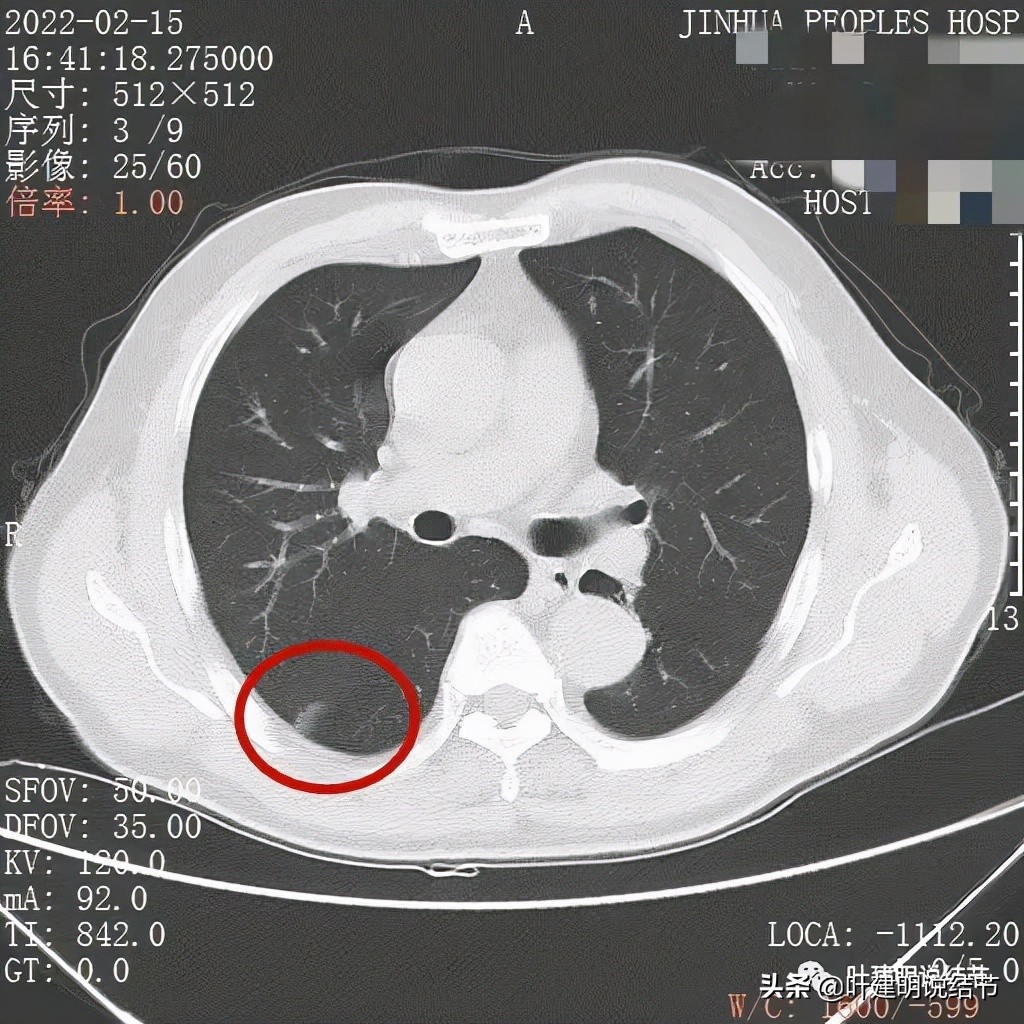

我们先来看下他的CT平扫5毫米层厚的图像:

病灶的部分边缘呈锯齿状,不平整,更谈不上光滑

病灶下缘显示与叶裂相接触处